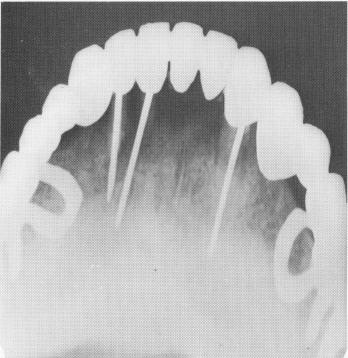

Fig. 13-41. A, A uniquely designed scalloped template with Gerber spring type attachments was cast. Below the template is seen the female attachment bar, which is processed to the prosthesis. B, An occlusal view of the template with both female attachments in place over the male attachment.

A

B